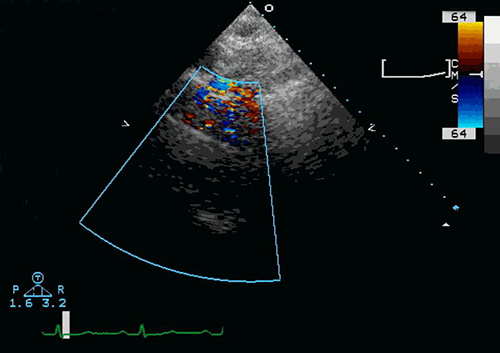

A standard echocardiogram (echo), also known as a transthoracic echocardiogram (TTE), is an imaging technology that uses ultrasound to create images of your heart. It is a diagnostic test used to examine the heart and its blood supply, determine how large the heart is, how well it contracts, and how the valves function.

An ultrasound probe is placed on the patient’s chest (thorax) and high frequency sound waves are used to create images of the heart. Doppler technology can also be used to analyze the speed and direction of blood flow. The images are displayed on a monitor and are digitally recorded.